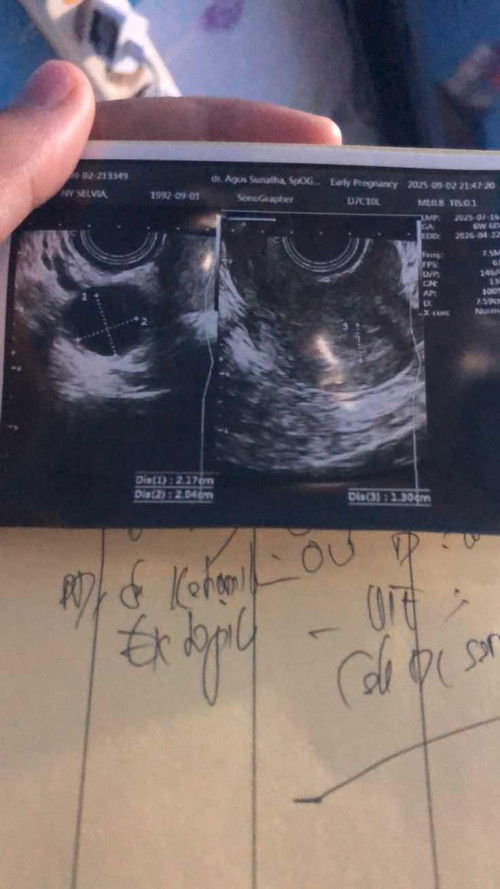

Hamil Ektopik di 7 week

Bunda, aku di diagnosa hamil di luar rahim setelah aku chek ke dokter krna aku flek . Pengalaman bunda bunda apa yg harus kita lakukan bun,ikut saran dokter kuret atau gimana bun . Dan janin belum ada bun. Keluhan keram juga hanya keram biasa